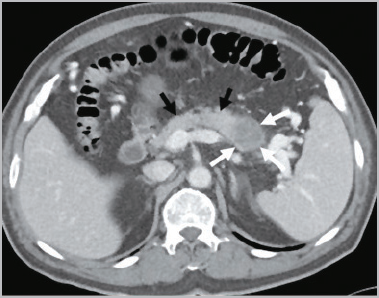

췌장은 위의 끝과 배꼽 사이 상복부에 위치한 소화기관으로 각종 소화효소와 인슐린을 분비하여 장내 음식물을 분해하고 혈당을 조절합니다. 췌장은 십이지장과 연결되어 있기 때문에 분비된 소화효소는 십이지장으로 방출되어 위에서 음식물과 섞이게 됩니다. 췌장은 해부학적으로 머리, 몸통, 꼬리로 나뉩니다.

머리는 담관과 연결되어 있기 때문에 머리에 있는 췌장암이 담관을 막아 황달을 유발할 수 있습니다. 꼬리는 비장과 연결되어 있습니다. 소장과 결장의 일부에 혈액을 공급하는 상부 장간막 동맥은 대동맥에서 분기되어 췌장 근처를 여행합니다.

췌장에서 발생하는 종양은 인슐린과 같은 호르몬을 분비하는 내분비세포에서 발생하는 종양의 10%, 소화효소를 분비하는 외분비세포에서 발생하는 종양의 90% 이상으로 구분된다. 내분비 세포에서 유래한 기능성 종양은 매우 드뭅니다. 외분비 세포에서 유래한 선암은 흔히 췌장암이라고 합니다.